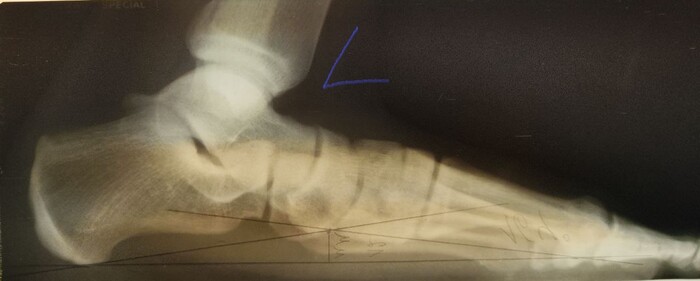

На Р-грамме левой стопы с нагрузкой: в структуре пяточной кости отмечается зона просветления костной ткани размером 29х27х17мм (точные размеры по данным КТ, которая была пройдена призывником),неправильной овоидной формы, с склеротическим контуром, соответствует кисте левой пяточной кости.

По заднему контуру таранной кости визуализируется добавочная кость- os trigonum размером 1.1х1.5см,наиболее вероятно вызывающая импиджмент-синдром заднего отдела голеностопного сустава.

Угол продольного свода левой стопы 160 град., высота 19 мм, соответствует продольному плоскостопию 3 ст. левой стопы.